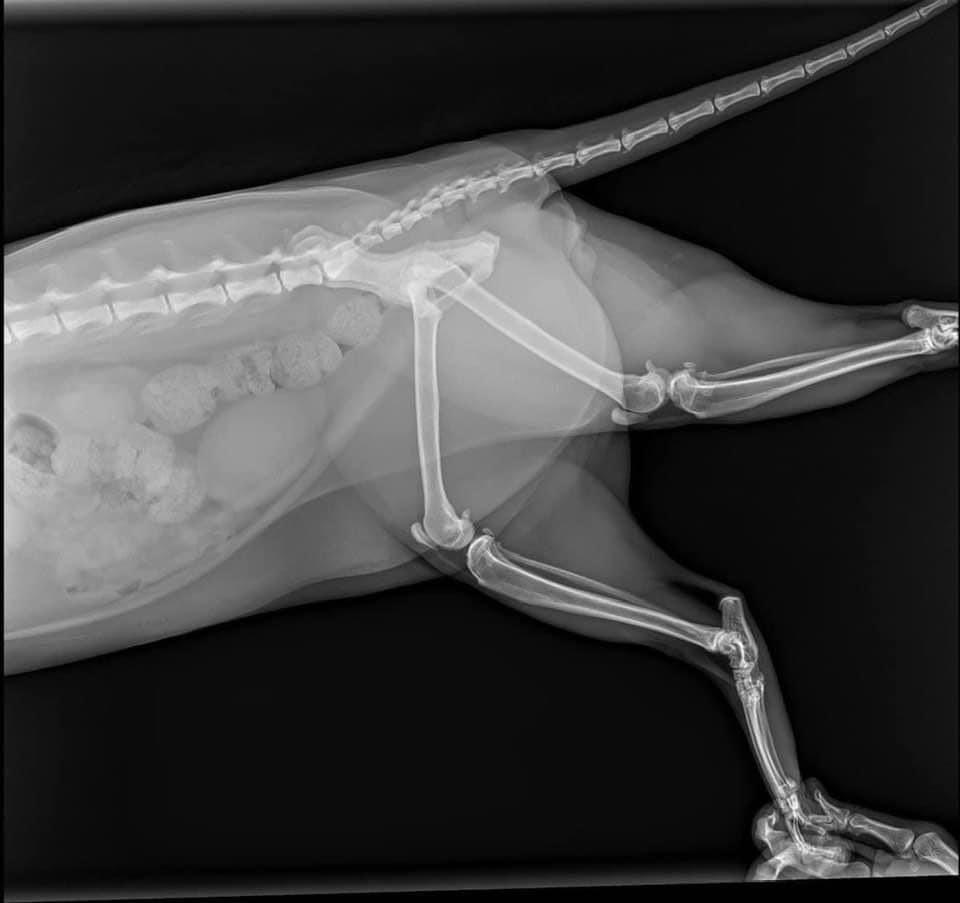

Sáng Chủ nhật đang ngủ ngon lành thì bảo vệ gọi xuống kiểm tra xe, bác còn bảo có con mèo bự làm hư xe, nghe mơ hồ như chiêm bao vậy, cho đến khi xuống xem mới biết. Bà mèo này nặng 8,5kg "hạ phàm" từ trên tầng xuống và làm vỡ kính xe. ![]()

Không chỉ vậy, giờ không tìm ra ai là chủ của nó, nên phải đưa nó đi khám bác sỹ thú y, chụp chiếu các kiểu nhưng may là nó không bị gì, chỉ bị xước 1 tý móng chân, có lẽ do lớp mỡ dày quá chăng?